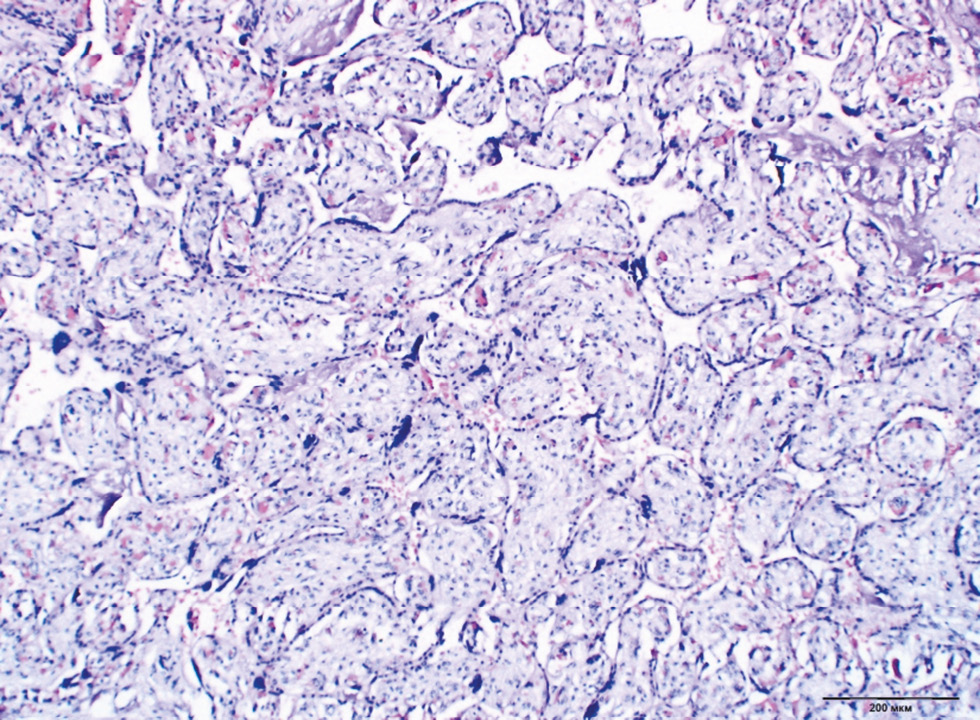

Chronic placental insufficiency was typical for all groups of DM and PE, in contrast to the control group (p < 0.0001). Placental insufficiency was registered in 39.6% of cases in Group 4 (type 2 DM on a diet), 37.2% in the type 1 DM group with MII, whereas pathological immaturity of villi was noted more often in the same groups (14.2% and 19.5%, respectively). In general, pathological immaturity of villi was typical for all groups of DM (9.5%–19.5%, p < 0.0001). The predominance of intermediate immature villi was a characteristic of type 1 DM with MII (13.3%, p = 0.036) (Fig. 1). The dissociated form of chronic placental insufficiency was most often detected in DM (16.3%–26.1%) (Fig. 2). The prevalence of sclerosed villi (0.4%–3.3%) and premature maturation of villi (0.4%–5.0%) were revealed less frequently. In the PE group, the premature maturation of villi was noted often (7.7%, p < 0.0001). In the control group, 93% of placentas corresponded to gestational age (Table 2).

Fig. 2. Dissociated chronic placental insufficiency in type 2 DM. Staining with hematoxylin and eosin, ×100